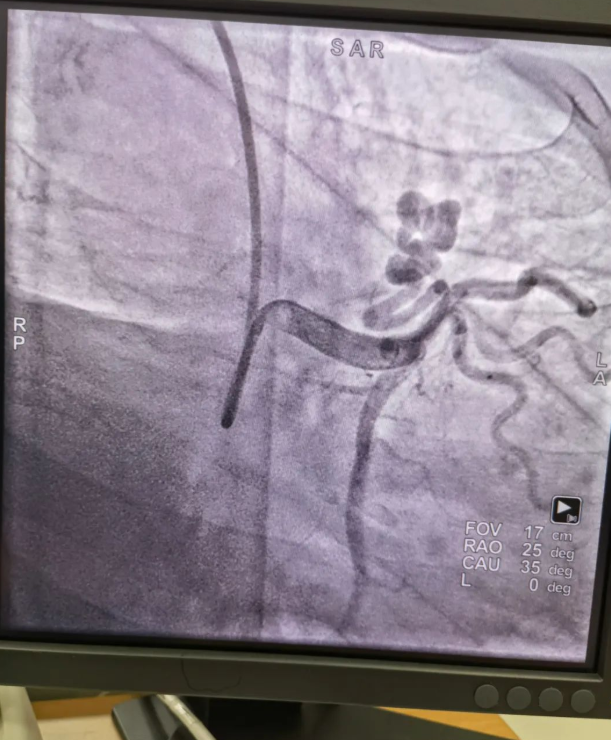

不久前,來(lái)自新疆的患者石先生去年至今反復(fù)胸悶、氣短、胸痛,就診于新疆某院,懷疑“冠心病”,住院行冠狀動(dòng)脈造影術(shù),石先生造影提示“冠狀動(dòng)脈肺動(dòng)脈瘺”,而他并非“冠心病”,所以給予的“冠心病”治療,效果不佳。出院后仍反復(fù)出現(xiàn)胸痛、胸悶、氣短等癥狀,經(jīng)親友介紹了解到西安國(guó)際醫(yī)學(xué)中心醫(yī)院心臟病醫(yī)院心臟內(nèi)科二病區(qū)曾廣偉主任,多年來(lái)潛心研究心臟病介入治療,成功主刀救治了許許多多高危復(fù)雜病例,尤其是在先心病及結(jié)構(gòu)性心臟病封堵,以及冠心病、心律失常射頻消融及起搏治療等方面積累了豐富的診療經(jīng)驗(yàn)。

此病例罕見,在曾廣偉從醫(yī)18年生涯里曾碰到有2個(gè)印象深刻的病例,患者分別是53歲和66歲,當(dāng)時(shí)建議患者入院進(jìn)行動(dòng)脈瘺的封堵術(shù),但患者和家屬考慮到這個(gè)手術(shù)案例極少,風(fēng)險(xiǎn)也高,均未接受手術(shù)治療建議,只是能采取藥物保守治療,出院后隨訪得知患者癥狀緩解效果不佳,后來(lái)在隨訪中也與53歲患者失去了聯(lián)系,而66歲患者因冠狀動(dòng)脈肺動(dòng)脈瘺出現(xiàn)反復(fù)心衰,在當(dāng)?shù)蒯t(yī)院藥物治療,短短2年時(shí)間,患者因?yàn)閯?dòng)脈瘺未及時(shí)手術(shù)失去了生命。所以此次患者石先生到訪,曾廣偉主任在詳細(xì)掌握病例資料基礎(chǔ)上,果斷建議進(jìn)行動(dòng)脈瘺的封堵術(shù)治療,為了提高手術(shù)成功率和精準(zhǔn)度,曾廣偉主任搜集相關(guān)診療資料,反復(fù)推演論證,經(jīng)過(guò)相當(dāng)充足的準(zhǔn)備工作,于5月18日成功進(jìn)行了封堵手術(shù),完全堵上了瘺口。

患者術(shù)后第2天,已經(jīng)沒(méi)有明顯的胸悶、氣短、胸痛等癥狀,目前身體狀態(tài)良好。本次手術(shù)曾廣偉主任及其團(tuán)隊(duì),采取從右手臂一根血管進(jìn)入,并在2小時(shí)之內(nèi)完美封堵,創(chuàng)口小,痛苦小。手術(shù)雖然難度大、風(fēng)險(xiǎn)高,相關(guān)案例也少,但是曾廣偉主任主刀即在巔峰,這樣一臺(tái)完美的手術(shù)靠的不是運(yùn)氣,是豐富的臨床手術(shù)經(jīng)驗(yàn),扎實(shí)的專業(yè)知識(shí)儲(chǔ)備,以及對(duì)醫(yī)療事業(yè)的孜孜追求。